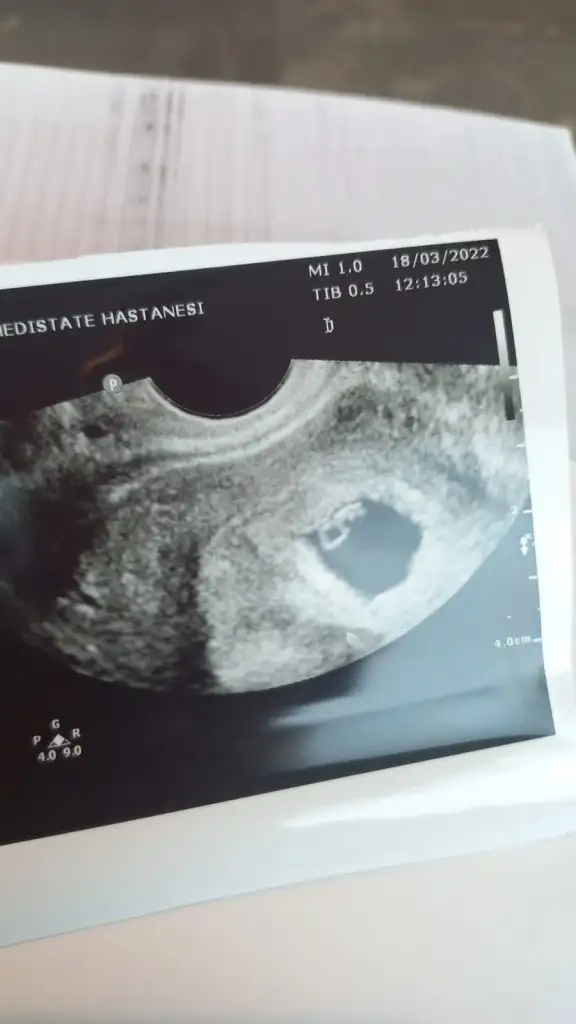

Anaaaaaaammmm bu ikinci keseyi 7+1 de mi gördün, ayy hep çok isterdim ikiz evladım olsun ne şanslın maşallahİlk fotoyu attığımda tek kese vardı ve erkek demiştin. Bugün gittim bi de ne göreyim çift keseVajinal ultrason biri 7+1 diğeri 6+6. Üstte sonradan beliren kesedeki bebiş solda gibi

Evett yaa 11 gün önce gittiğimde tekti. Çift embriyo transfer edilmişti. Hayatımızın şoku oldu saatlerce ağladık. Doktorum 1 nisan şakası değil diyoAnaaaaaaammmm bu ikinci keseyi 7+1 de mi gördün, ayy hep çok isterdim ikiz evladım olsun ne şanslın maşallahkuzu ikiside farklı cinsiyetler gibi duruyor biri kız biri erkek gibi. İlerleyen fotolarını da at emin olalım